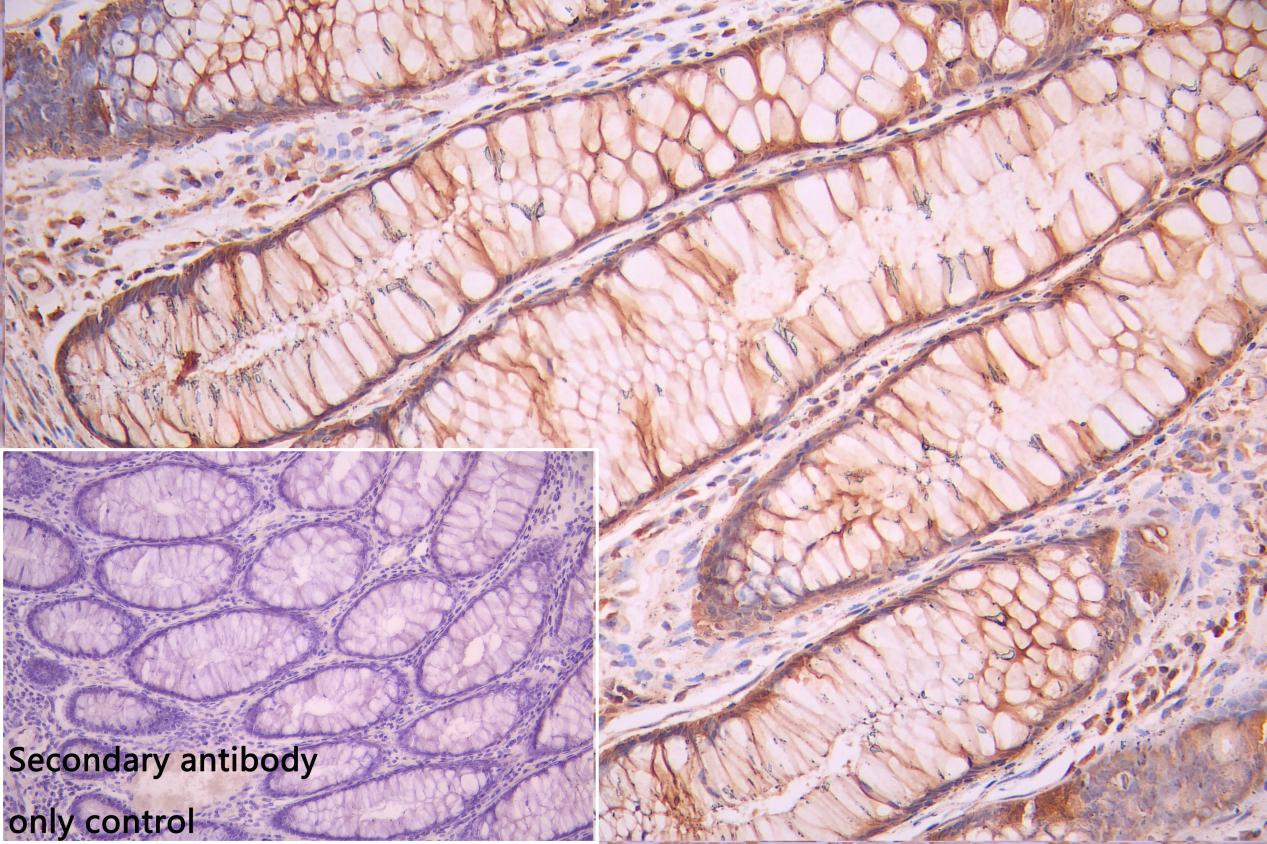

IHC image of CSB-PA896505DSR2HU diluted at 1:50 and staining in paraffin-embedded human colorectal cancer performed on a Leica BondTM system. After dewaxing and hydration, antigen retrieval was mediated by high pressure in a citrate buffer (pH 6.0). Section was blocked with 10% normal goat serum 30min at RT. Then primary antibody (1% BSA) was incubated at 4°C overnight. The primary is detected by a Goat anti-rabbit polymer IgG labeled by HRP and visualized using 0.05% DAB. Secondary antibody only control: uses 1% BSA instead of primary antibody